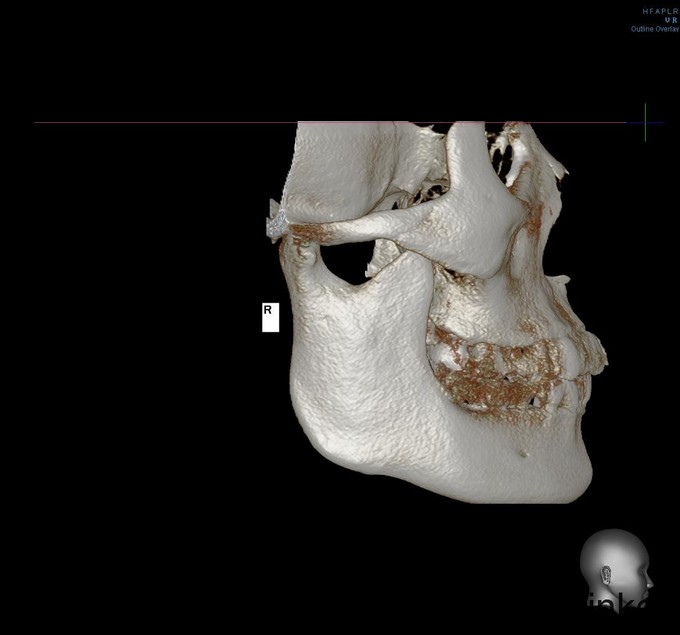

发现左下颌骨局部肿大6年,青年女患者,慢性病程。患者于6年前无明显诱因发现左下颌骨局部肿大,逐渐加重,无明显疼痛、口角麻木等不适。今为进一步治疗来我院就诊,门诊以"左下颌骨骨纤维异常增殖症"收入院

颌面部左右不对称,左下颌区较右侧肥大,开口型正常,开口度4.0cm,双侧关节无明显压痛、弹响,双侧髁突动度左右基本对称。左下颌骨约35至磨牙后区颌骨肿大,前庭沟变浅,同时舌侧可及肿大,质地硬,黏膜无破溃流脓,牙齿无明显松动。

诊断:左下颌骨骨纤维异样增殖症,全麻下行“左下颌骨整形行性切除+左下颌角修整术+邻近瓣转移修复术”